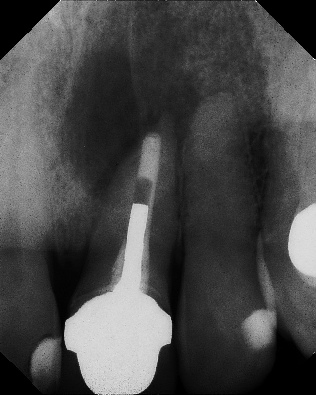

Apicoectomy - Surgical Root Canal Pre-op (post trauma) Coronal segments obturated Apical segments surgically removed 3 years